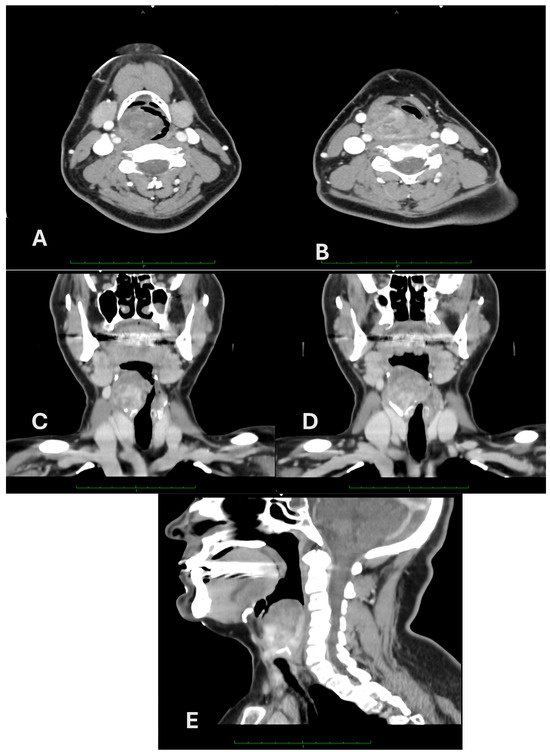

2. Case Report